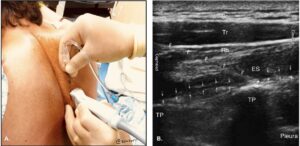

Injection technique demonstrated in picture A, needle placement visualized in picture B between the transverse process and erector spinae (Highland US).12